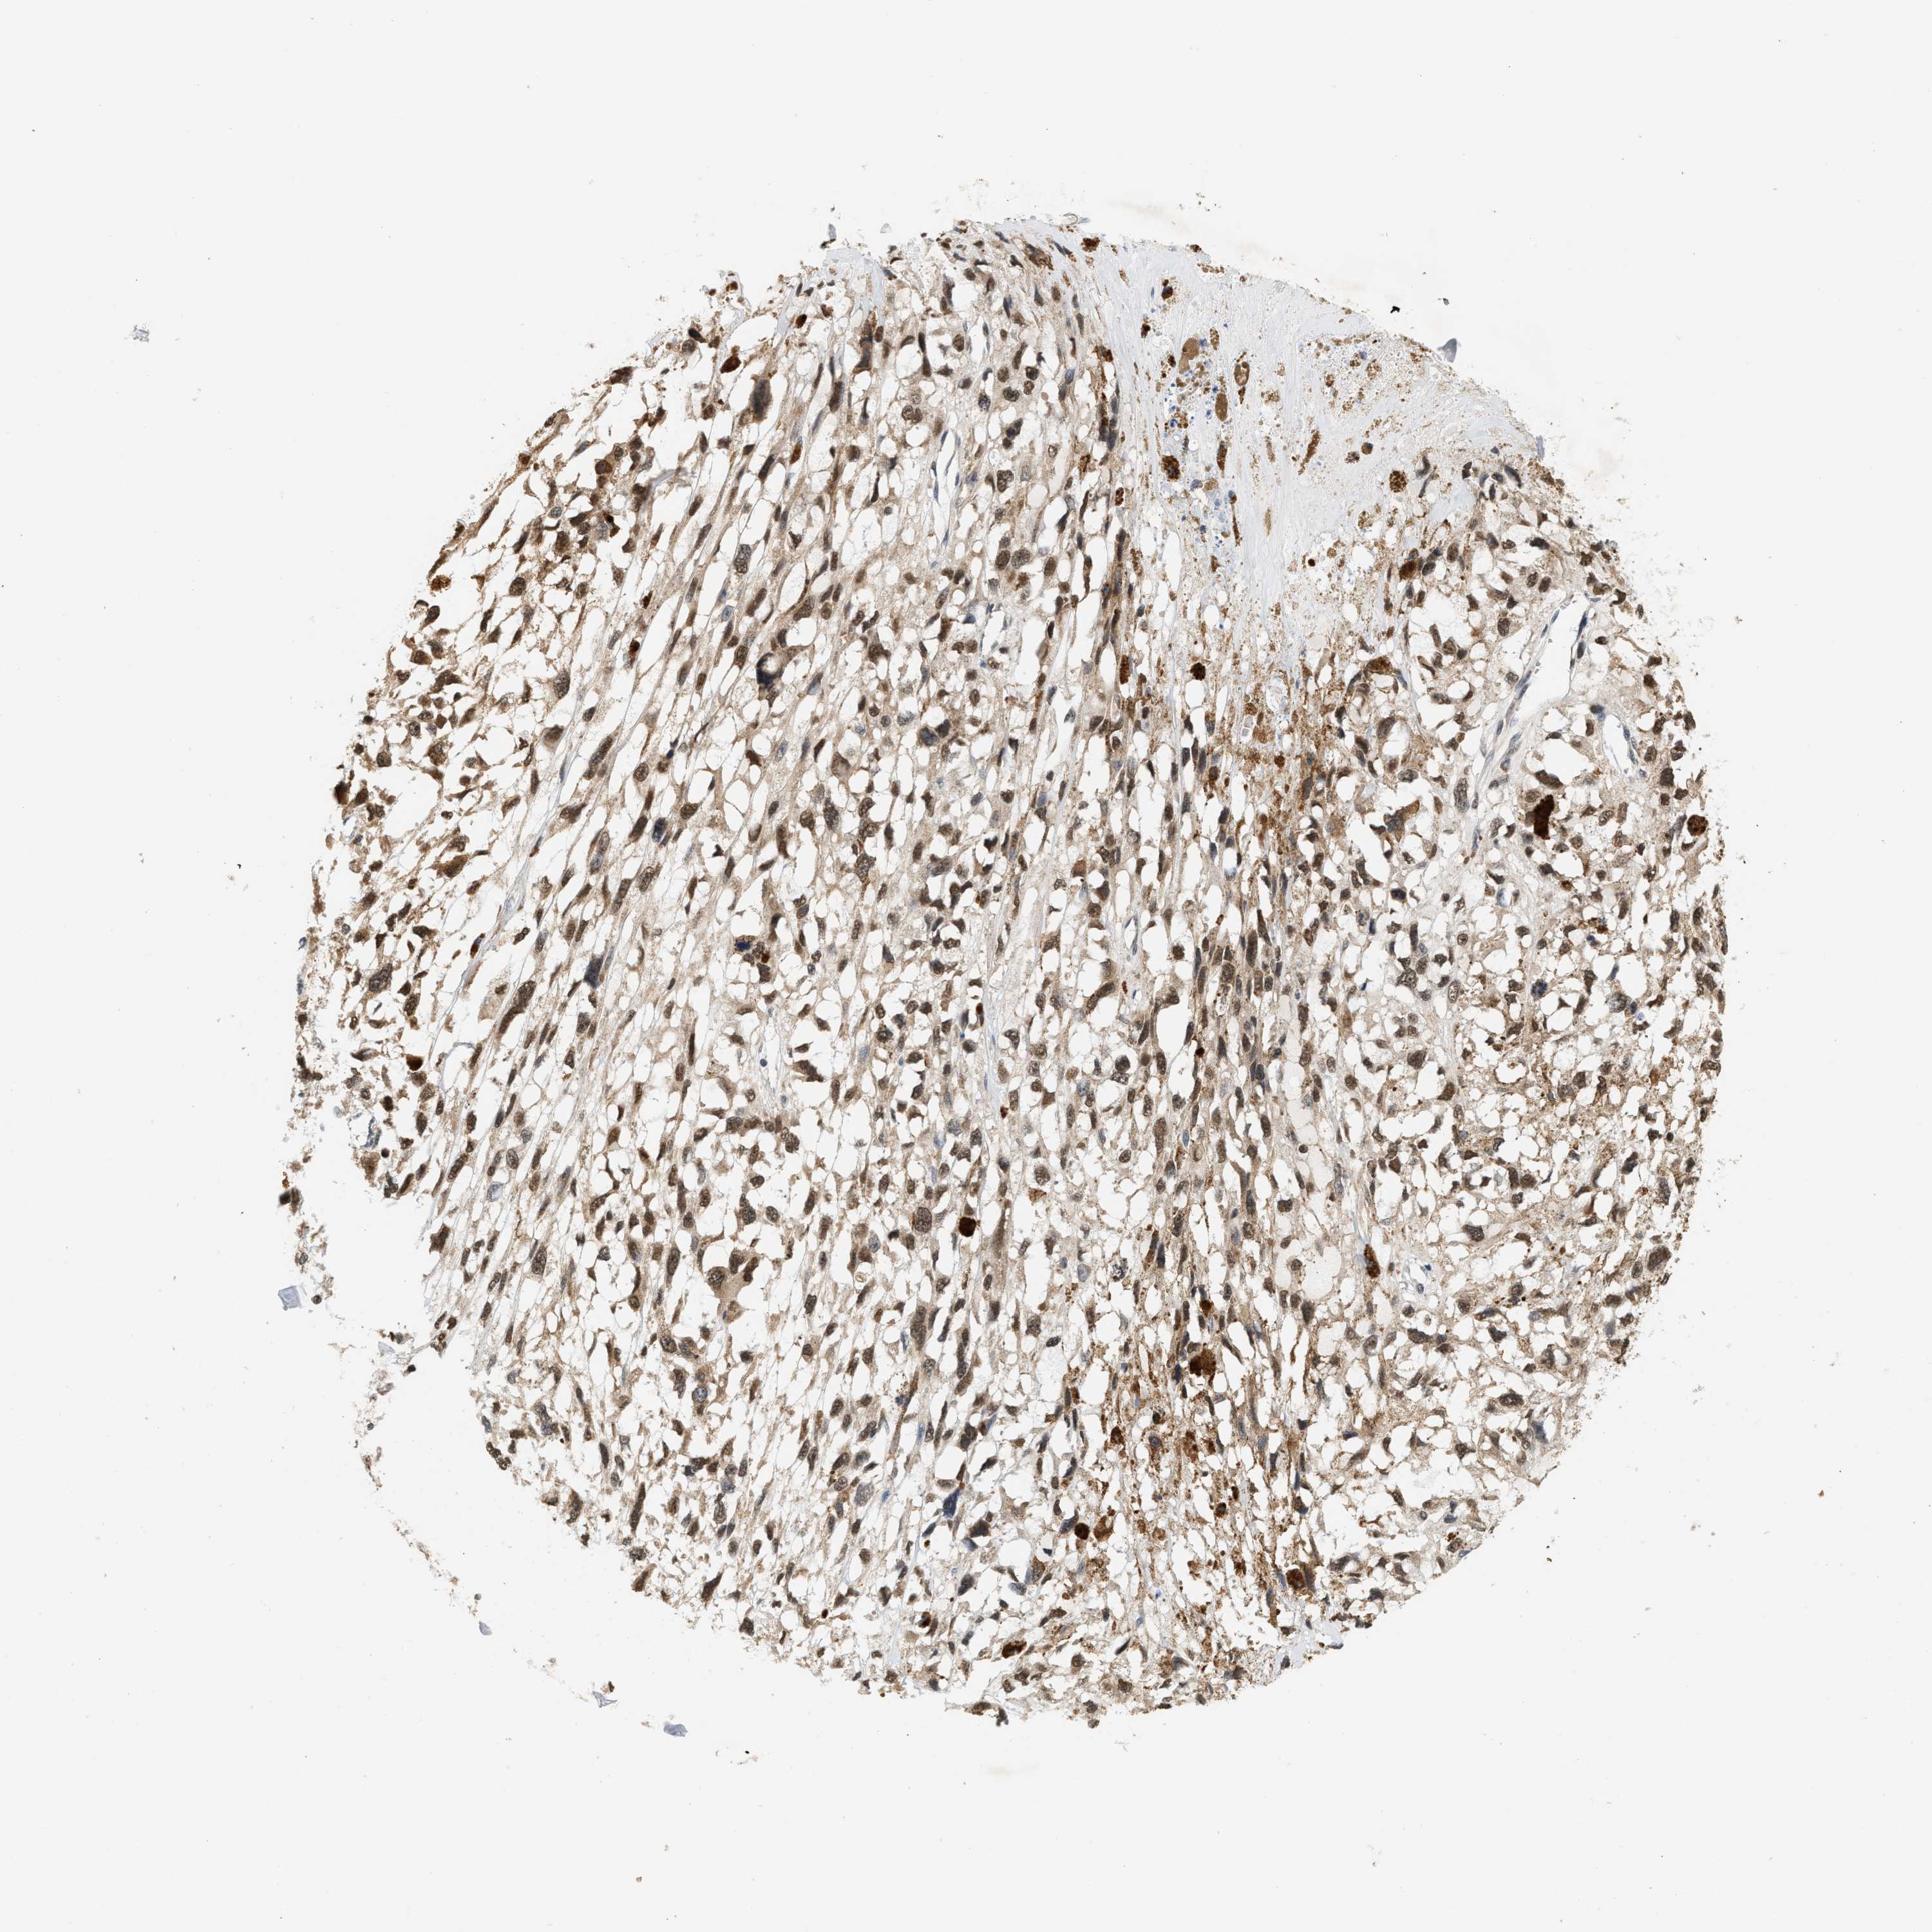

MELANOMA - Protein expressioni

A mouse-over function shows sample information and annotation data. Click on an image to view it in a full screen mode. Samples can be filtered based on level of antibody staining by selecting one or several of the following categories: high, medium, low and not detected. The assay and annotation is described here.

Note that samples used for immunohistochemistry by the Human Protein Atlas do not correspond to samples in the TCGA dataset.

Antibody stainingi

Antibody staining in the annotated cell types in the current human tissue is reported as not detected, low, medium, or high, based on conventional immunohistochemistry profiling in selected tissues. This score is based on the combination of the staining intensity and fraction of stained cells.

Each image is clickable and will lead to virtual microscopy that enables deeper exploration of all samples and also displays staining intensity scores, fraction scores and subcellular localization as well as patient and tissue information for each sample.

Antibody HPA020999

Antibody HPA023995

Staining

High

Medium

Low

Not detected

Intensity

Strong

Moderate

Weak

Negative

Quantity

>75%

75%-25%

<25%

None

Location

Nuclear

Cytoplasmic/membranous

Cytoplasmic/membranous,nuclear

Malignant melanoma, NOS

Malignant melanoma, Metastatic site